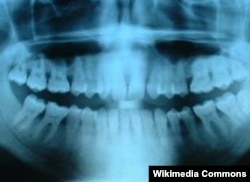

Дүйнө калкында эң кеңири тараган тиштин дарты – кариес. Мындан жылына дүйнө боюнча эки жарым миллиард адам жабыркайт.

Кариес бир нече баскыч менен оорлошот. Биринчиден, тишти каптаган эмаль бузулганда, көзгө көрүнбөгөн жарака кетип, андан тиштеги минералдар сыртка чыга баштайт. Эгер тиш көпчүлүк минералдарын жоготсо, ал кариеске чалдыгат. Кадимки дарылоо ыкмасында "курт жеген тиш" атайын машине менен тазаланып, тиштин нервдери дарыланып, ал эми кариес баскан тиш – пломба менен жамалат. Тиштин сөөгү чирип түшүп, каналдары катуу сезгенген учурда ал тургай тишти жулдурууга туура келет.